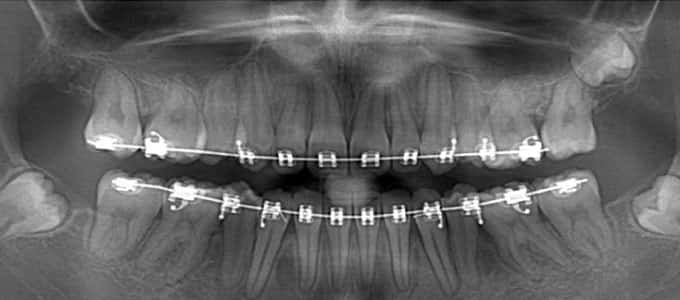

Tratamentul ortodontic este un proces biologic complex care include modificări ale oaselor maxilare, faciale și ale țesuturilor moi pe măsură ce dinții sunt mișcați în noile poziții.

Tratamentul ortodontic nu este o soluție rapidă. Acesta începe întotdeauna cu o examinare minuțioasă a dinților, a buzelor și a întregului aspect facial, sunt necesare radiografii si fotografii de diagnostic. Din aceste informații detaliate medicul ortodont dezvoltă un plan de tratament personalizat.